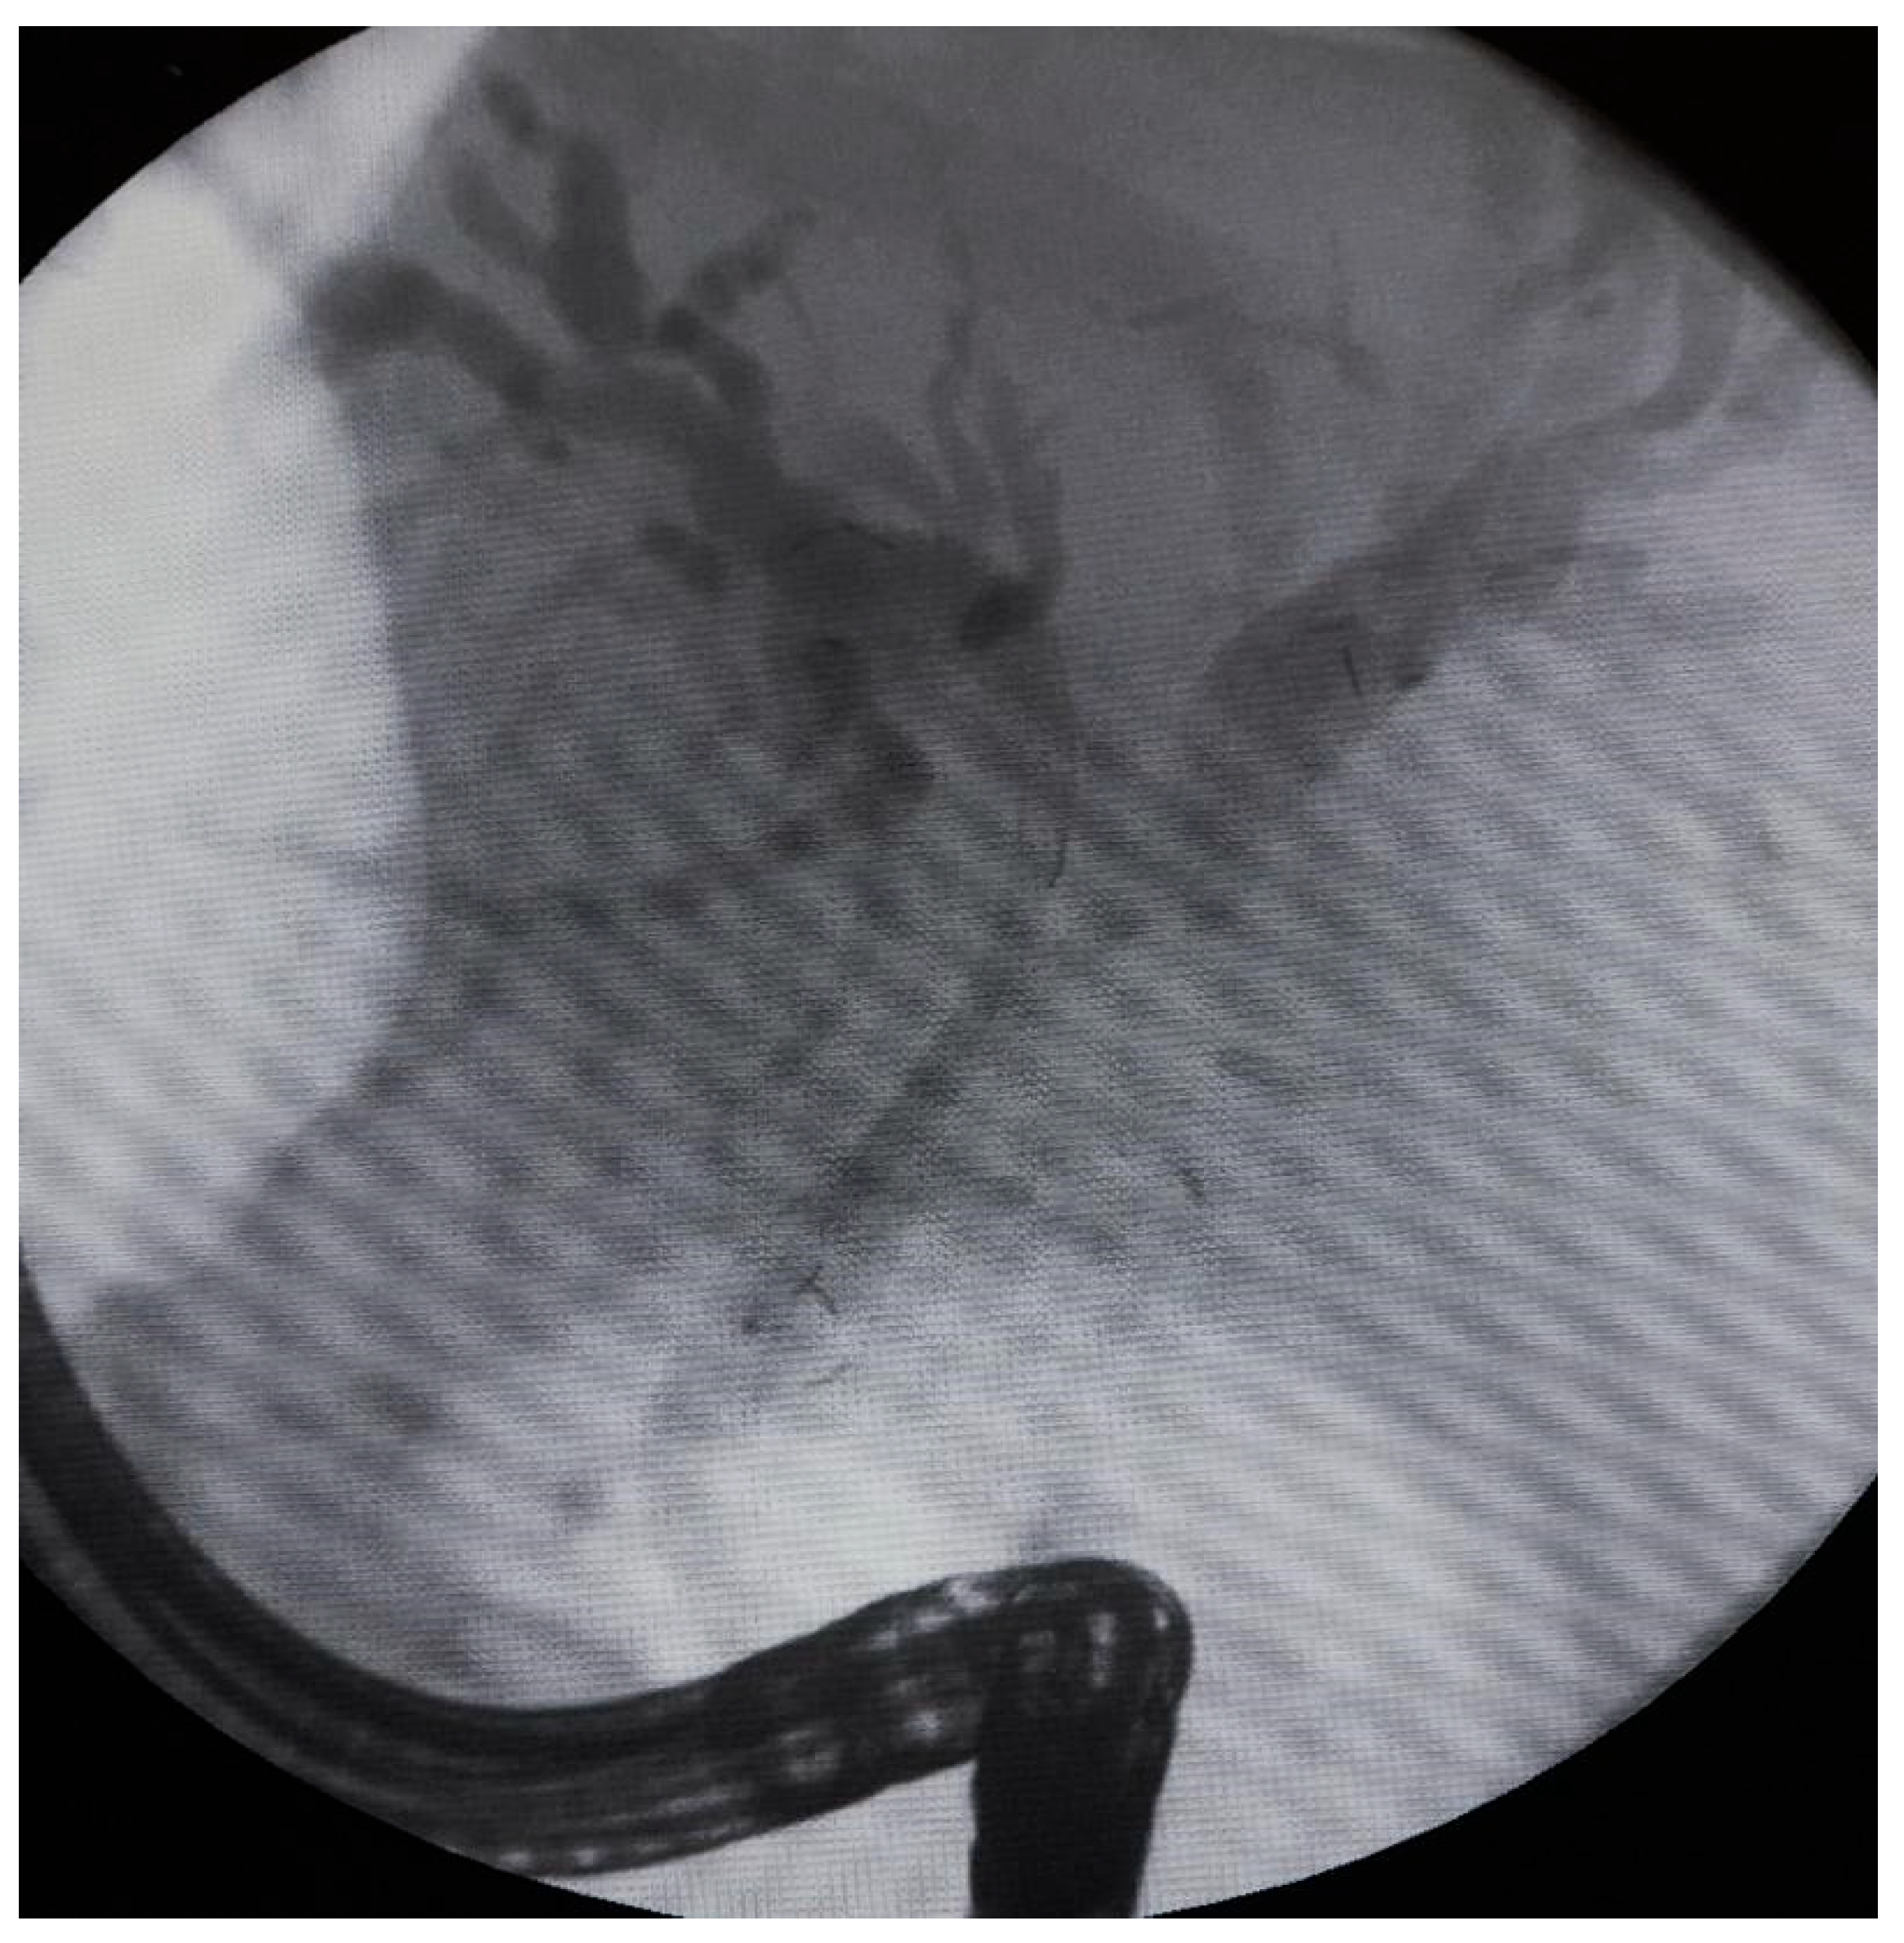

Patients receiving only one ablation treatment with the stricture in the hilar region received double uncovered SEMS in the Y (stent-in-stent) or X (side-by-side) configuration. In difficult hepatic duct cannulations, the X configuration was preferred; otherwise the Y configuration was used, as it is considered beneficial during reinterventions.

The following stents were used for the procedure: uncovered SEMS (10 × 80 mm, 10 × 60 mm, 10 × 100 mm), Large Cell D-type stents (LCD) (10 × 60 mm), fully covered SEMS (8 × 80 mm), Amsterdam-type plastic stents (12 cm 10 Fr, 9 cm 10 Fr, 12 cm 8.5 Fr, 12 cm 7 Fr), and self-expandable BIL-0-10-60-RP stents. Figure 2, Figure 3 and Figure 4 present the RFA catheter and stents’ configurations (Figure 2, Figure 3 and Figure 4).

Figure 3. Side-by-side (stent-by-stent) bilateral uncovered SEMS configuration for malignant hilar obstruction. This configuration may be preferred when selective cannulation of both hepatic ducts is technically challenging, allowing independent deployment of two stents.

Figure 4. Stent-in-stent (Y) bilateral uncovered SEMS configuration for malignant hilar obstruction. This configuration is commonly used when bilateral access is achievable and may facilitate endoscopic reintervention through the stent mesh if needed.